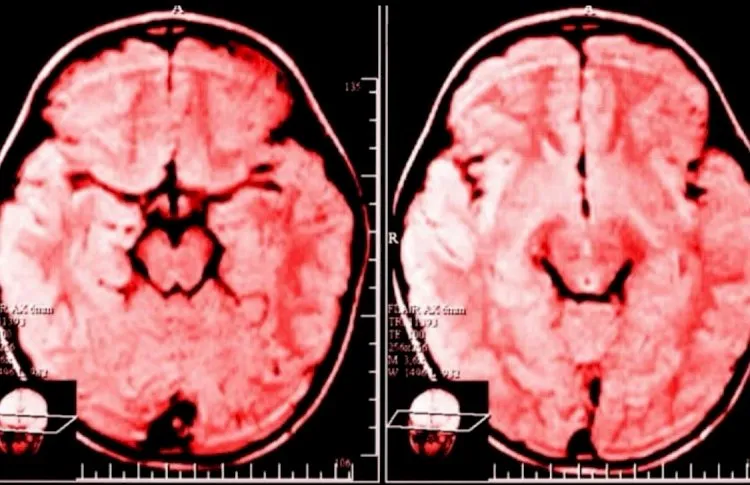

O cérebro humano é altamente plástico, o que significa que ele pode se adaptar e modificar sua estrutura ao longo do tempo, com base nas experiências e estímulos aos quais é exposto. O conceito de neuroplasticidade, popularizado pelo cientista Donald Hebb, é fundamental para entender como o hábito de reclamar pode afetar nosso cérebro. Segundo Hebb, “sinapses que disparam juntas, se mantêm juntas”, ou seja, os circuitos neurais relacionados a um determinado pensamento ou emoção se tornam mais fortes e fáceis de ativar à medida que são repetidos. Quando uma pessoa se habitua a reclamar, as conexões neuronais associadas a esses sentimentos negativos se tornam mais robustas, criando uma mentalidade mais focada no problema, no que não está funcionando.

Além disso, esse padrão de pensamento negativo pode afetar nossa personalidade. A neuroplasticidade sugere que, à medida que nossa mente se acostuma a focar em aspectos negativos, o cérebro “prioriza” essas conexões, tornando-as mais automáticas e difíceis de superar. Isso não só afeta o nosso estado emocional, mas também a nossa percepção da realidade, tornando mais difícil encontrar soluções ou adotar uma perspectiva otimista.